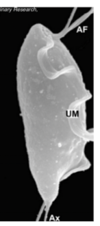

giardia trophozoite

giardia trophozoites look

A

pear shaped

x2 size of a red blood cell

2 nuclei, median body and axostyle

free flagellae and sucking disk